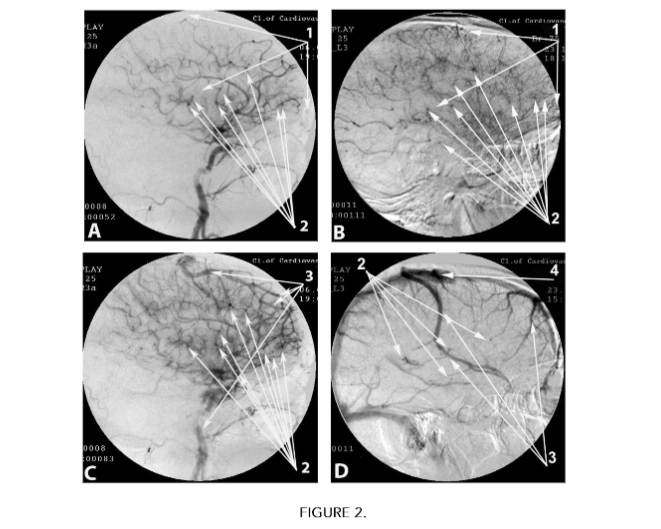

Cerebral MUGA with digital image processing revealed “Dyscirculatory angiopathy of Alzheimer’s type” (DAAT):

- A decrease in the number (reduction) of capillaries with the development of hypovascular zones in the temporal and frontoparietal regions were detected in all 93 (100%) cases (Table 2), (Fig. 2 A(1), Fig. 2 B(1)).

- Local arteriovenous shunts in the basins of the anterior villous arteries supplying the temporal lobes, as well as in the basins of the distal arterial branches supplying the frontoparietal regions of the brain were detected in all 93 (100%) cases (Table 2), (Fig. 2 A(2), Fig. 2 B(2), Fig. C(2), Fig. D(2)).

- Local early discharge of arterial blood into the venous bed, accompanied by simultaneous contrasting of arteries and veins, were detected in all 93 (100%) cases (Table 2), (Figure 2 C(3)).

- Abnormally dilated venous trunks, into which blood flows through arteriovenous shunts of the temporal and frontoparietal regions, were detected in 84 (90.32%) cases (Table 2), (Fig. 2 C(3), Fig. D(3)).

- Abnormal stasis of venous blood at the borders of the frontal and parietal lobes, caused by increased blood flow through arteriovenous shunts, was detected in 85 (91.40%) cases (Table 2), (Fig. 2 D(4)).

Cerebral MUGA of patients with Dyscirculatory angiopathy of Alzheimer’s type (DAAT)

A. Arterial phase:

- Capillary reduction with development of hypovascular zones in the temporal and frontoparietal regions.

- Local arteriovenous shunts.

B. Parenchymal stage:

- Local arteriovenous shunts.Simultaneous contrast of arteries and veins.

D. Late venous phase.

2. Local arteriovenous shunts.

3. Abnormally dilated venous trunks.

4. Abnormal venous congestion.

As in our earlier works¹³,²³,²⁶, this study shows that patients from Test Group 1 have virtually no signs of intracerebral atherosclerosis (Table 2). The existing cerebrovascular disorders and CSVD have their own clear specificity and are manifested in Dyscirculatory angiopathy of Alzheimer’s type (DAAT), which is an important factor in the development of AD (Table 2). In all patients from Test Group 1, the main manifestation of DAAT development is a decrease in the number (reduction) of capillaries, first in the temporal and then in the frontoparietal cerebral lobes with the formation of hypovascular zones in these areas (Fig. 2 A(1), Fig. 2 B(1)), (Table 2). These changes are not a consequence of stenosis or occlusion, they have their own specificity, and, unlike atherosclerosis, are hereditary (Table 2).

Reduction of capillaries, their thinning, and a decrease in further branching lead to disruption of cerebral hemodynamics, reduction in the distal inflow of arterial blood with the development of hypoxia specific to AD. The blood, flowing through intracerebral arterial branches, is unable to pass through the reduced number of arterioles and capillaries. As a result, in the temporal and frontoparietal regions, fairly large arteriovenous shunts develop, through which “excess” arterial blood is discharged into the venous bed (Fig. 2 A(2), Fig. 2 B(2), Fig. 2 C(2), Fig. 2 D(2)), (Table 2). The opening of arteriovenous shunts is a natural protective reaction of the body to the disruption of blood flow through the distal arteries and capillaries. As a result of the active flow of arterial blood into the venous bed, lateral, abnormally dilated venous trunks develop (Table 2). During MUGA, this is manifested in simultaneous contrasting of arteries and veins (Fig. 2 C(3), Fig. 2 D(3)). Active flow of arterial blood into the venous bed leads to venous overflow and stasis (Fig. 2 D(4)), (Table 2). These changes cause further increase in cerebrovascular dysfunction, which causes disturbances in metabolic processes in cerebral tissue. Arterial, capillary and venous changes in DAAT are equally determined at all stages of AD regardless of the severity of the disease, which indicates the congenital nature of the changes (Table 2).